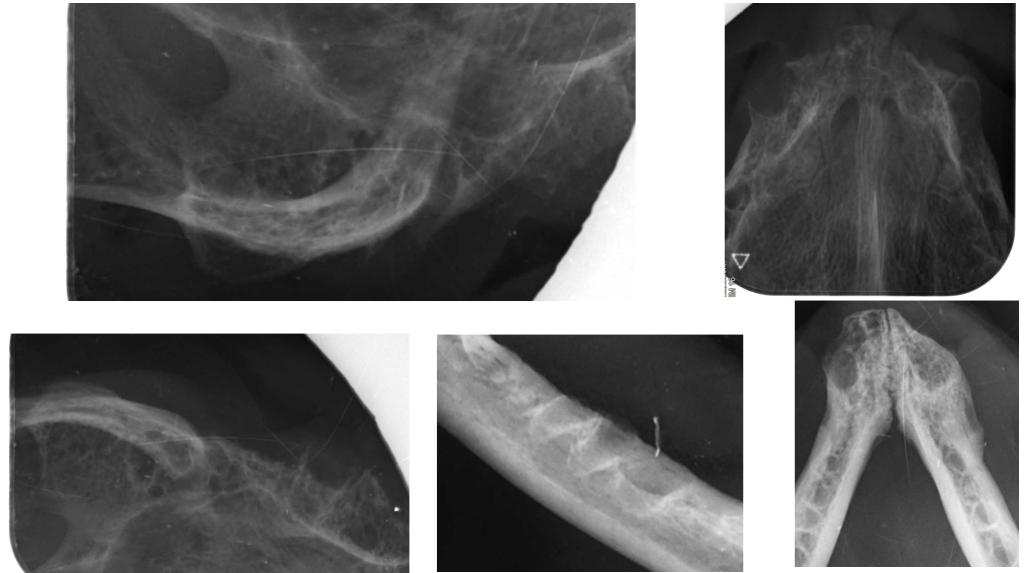

Лечение. Выполнены тотальное удаление зубов под контролем рентгенографии и альвеолопластика. Проведены кюретаж лунок и наложение швов (фото 4, 5).

Результат лечения. После операции пациент не демонстрировал симптомов боли, у него улучшился аппетит, появилась прибавка в весе. На контрольных осмотрах наблюдалась положительная динамика состояния слизистой оболочки полости рта (фото 6, 7), поэтому к дополнительным методам лечения не прибегали.

Лечение. Проведены тотальное удаление зубов под рентгенологическим контролем, альвеолопластика, кюретаж и наложение швов (фото 10, 11).

Результат лечения. Спустя 4 месяца контрольный осмотр показал улучшение качества жизни пациента с положительным ответом на хирургическое лечение (фото 12).